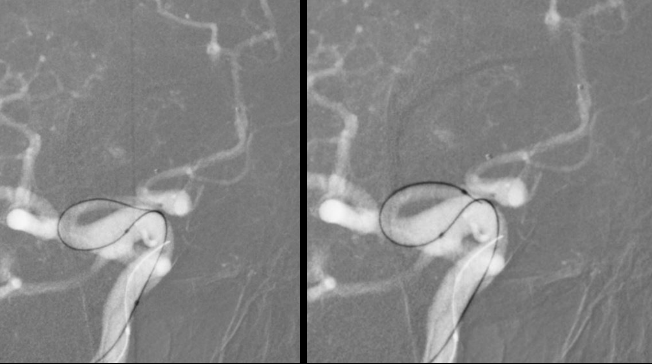

外院DSA

右颈动脉

左椎动脉

左颈动脉

诊断:右侧前交通动脉瘤

患者在全麻下、多参数监护仪监测下行前交通动脉瘤经右侧颈内动脉支架辅助下栓塞术。全麻后,常规消毒销巾,采用改良seldinger技术穿刺右侧股动脉或功,置入6F动脉鞘。黑泥鳅导丝及多功能导管带领6F MPD导管达到右侧颈内动脉岩段,行造影见∶前交通动脉瘤,瘤体3.5 mm*5.1 mm。在路图引导下,徵导丝(Synchro 0.014 in*200 cm)带领弹支架微导管(SL-10)到右侧大脑前动脉A2段,退出微导丝。微导丝(Synchro 0.014 in*200 cm)带领弹簧圈微导管(eV3 Echelon-10)到达前交通动脉瘤体内,退出微导丝。经弹簧圈微导管填入首枚弹簧圈(Codman COMPLEX XTRASOFT3 mm*6 cm)成篮良好,在路图引导下在支架管内输送支架(Neuroform Atlas 3.0 mm*21 mm)并释放完全覆盖动脉瘤颈,造影可见支架打开良好解脱首枚弹备圈,沿弹簧圈导管继续填入弹簧圈(可见护理记录单)间断造影确保双侧大脑前动脉血流通畅。右侧颈内动脉造影确认∶前交通动脉瘤填塞致密,双侧大应前动脉血流通畅。手术结束。右侧股动脉鞘处用血管封堵器(Coxrds Exoseal 6F)封堵,并压迫器持续压迫。木后患者清醒。